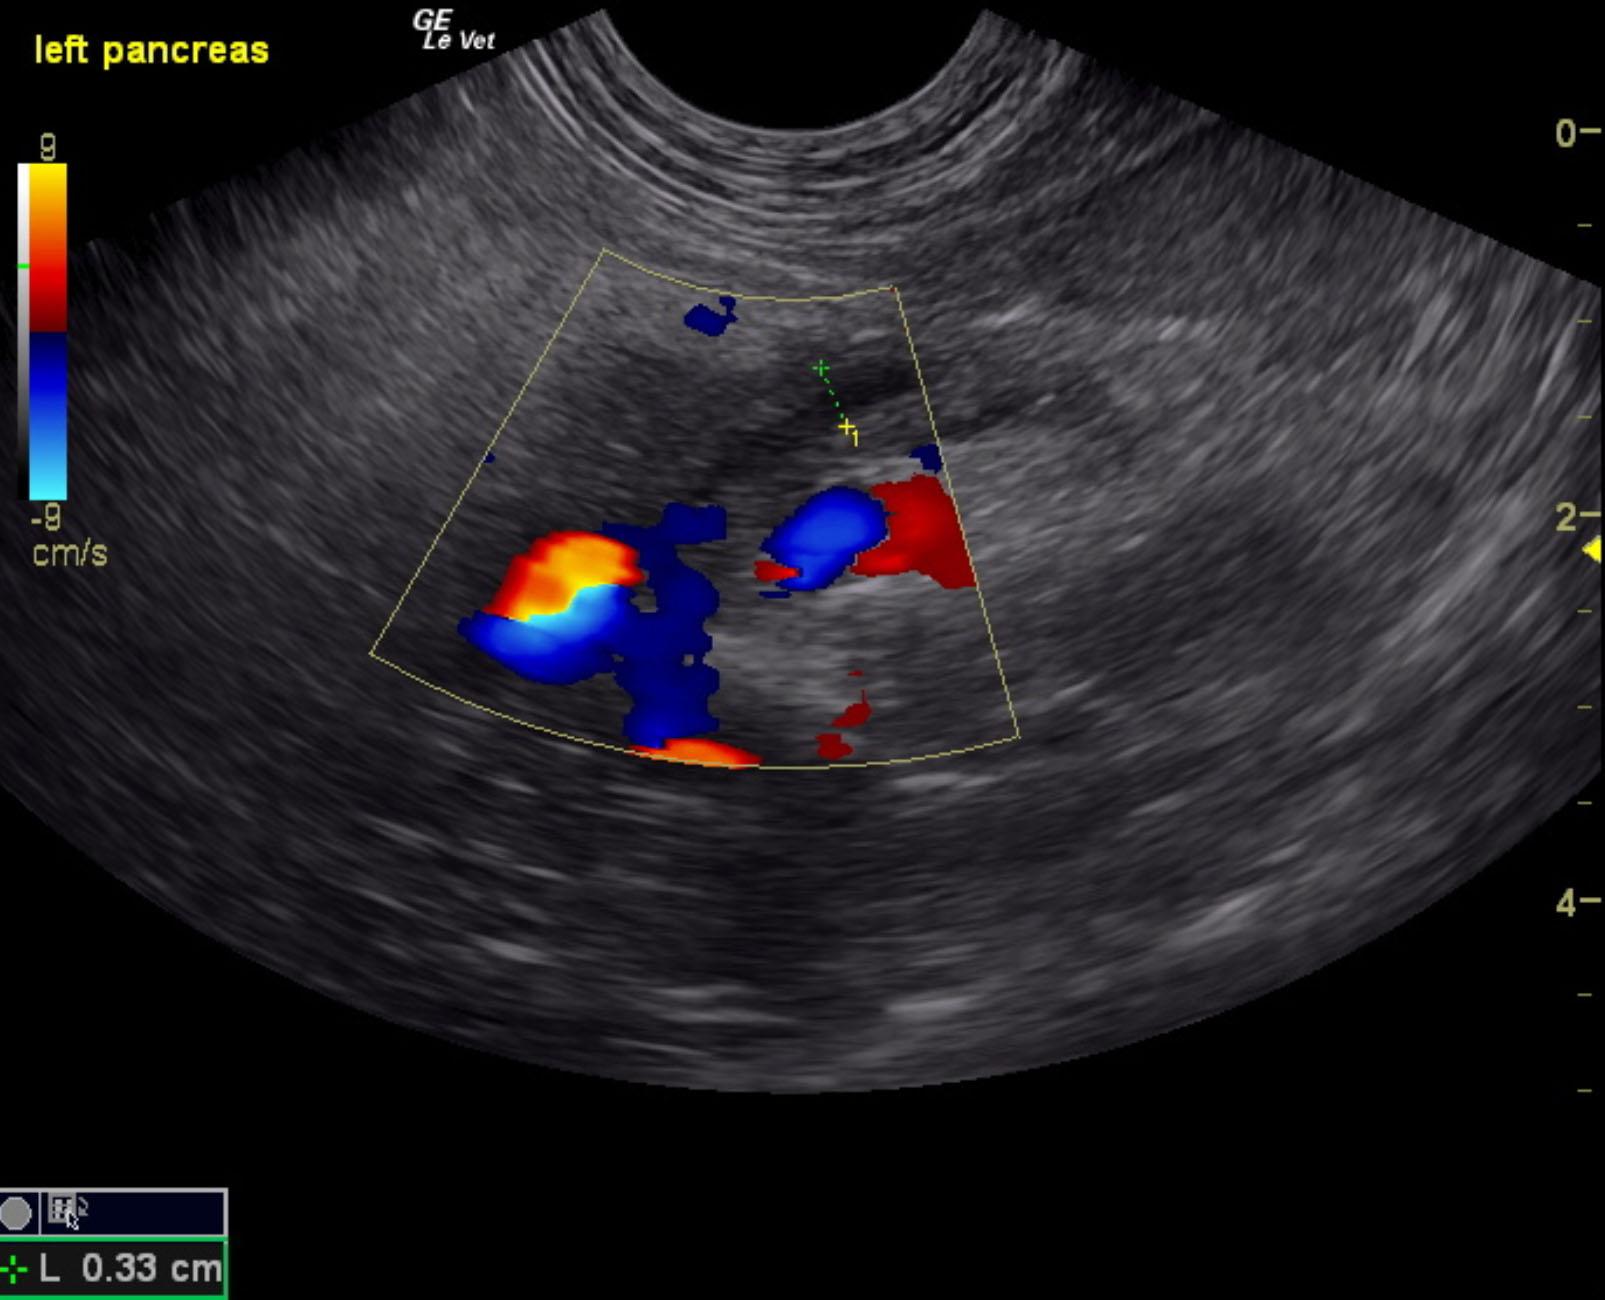

A 10-year-old female spayed DSH cat was presented for evaluation of intermittent diarrhea, weight loss, and anorexia. Blood work was unremarkable.

A 10-year-old female spayed DSH cat was presented for evaluation of intermittent diarrhea, weight loss, and anorexia. Blood work was unremarkable.